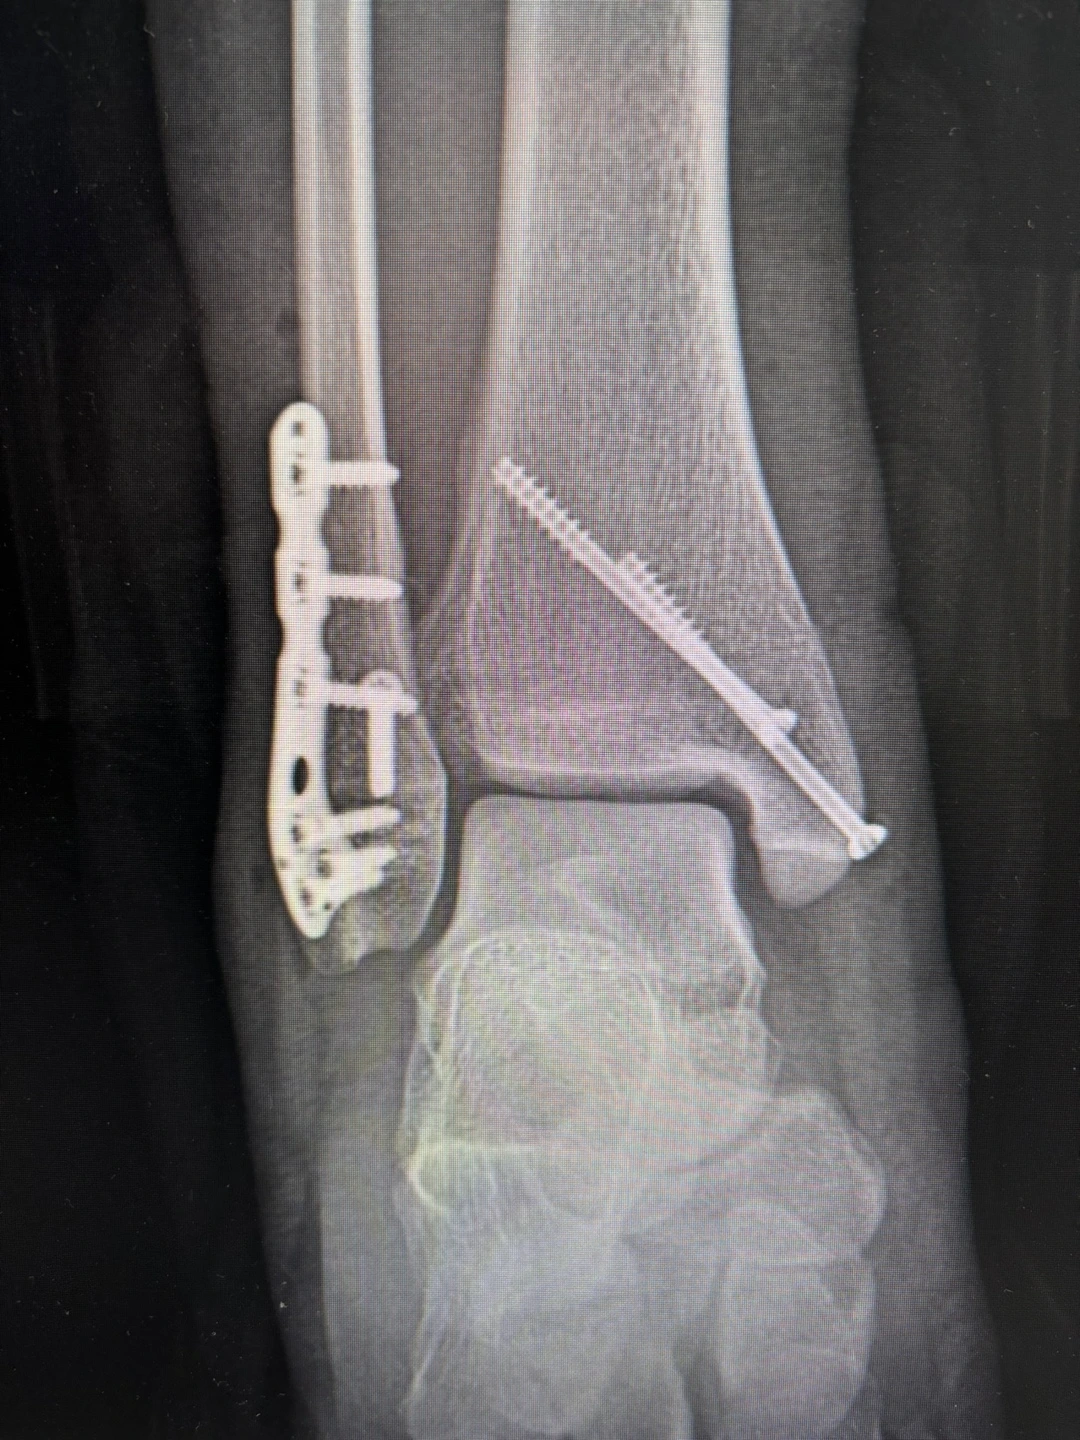

양측 복사 골절. 원위 경비 인대의 파열 및 불안정성

조인협 러너가 2024년 초겨울 받아 든 수술확인서 병명 란에 적힌 내용이다. 그는 이 수술로 인해 몇 개월의 재활로 인한 러닝 공백기를 가졌다. 러너에게 신체 일부, 특히 발을 다치는 것은 가수에겐 목소리를 앗아가는 것과 비슷할 것이다. 게다가 조 러너는 2023년 JTBC 마라톤에서 풀코스 3시간 12분을 기록한 러너이자 아식스 에이레이서 1기로 뽑힌 바 있는 ‘뛰조’(인스타그램 계정 @ddwi_jo)다. 런생뿐 아니라 일상에도 영향을 미치기에 어쩌면 인생의 위기라고도 볼 수도 있었다.

수술 후 엑스레이 사진. <출처 조인협 러너>

하지만 그는 2025 JTBC마라톤 3시간 4분 58초라는 기록으로 약 1년 반만에 재기에 성공했다. 그것도 2년 전보다 뛰어난 기량으로 말이다. 그의 다음 목표는 2026년 서울마라톤 풀코스 3시간 이내 완주다. 그는 어떻게 부상을 극복하고 다시 웃을 수 있었을까. 그동안 어떤 변화를 겪었을까.